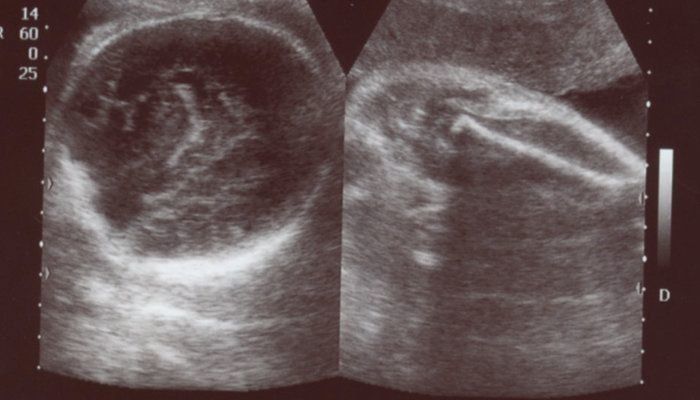

チャーミー小結さんの妊娠32週目のエコー写真

妊娠32週目。赤ちゃんの体重1915g。この頃の楽しみは医師軍団による回診で、ドラマ「白い巨塔」の再現VTRを見ているようでした。実家の母に頼んでウエストサイズ100cmのパジャマを作って送ってもらいました。